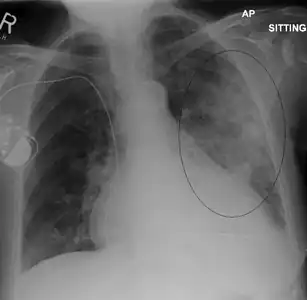

AP CXR showing left lower lobe pneumonia associated with a small left sided pleural effusion

Left upper lobe pneumonia with a small pleural effusion.